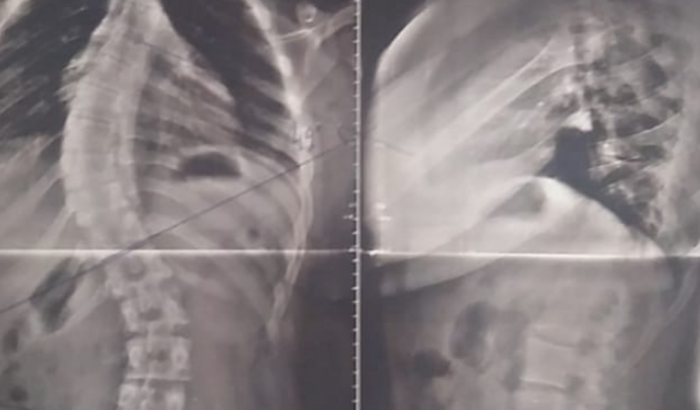

Meu nome é Rosangela e criei está vaquinha, pois preciso arrecadar R$5800,00, para comprar um colete 3D para minha filha Isabella de 13anos, pois a mesma se encontra com uma escoliose dorsal direita lombar esquerda com ângulos de Cobb medindo cerca de 43 e 35 graus respectivamente e ela sente muita dor. Com o uso frequente deste colete ela poderá ter a sua coluna estabilizada para realizar as atividades que todo jovem deseja. Desde já agradeço a todos que contribuírem e divulgarem.